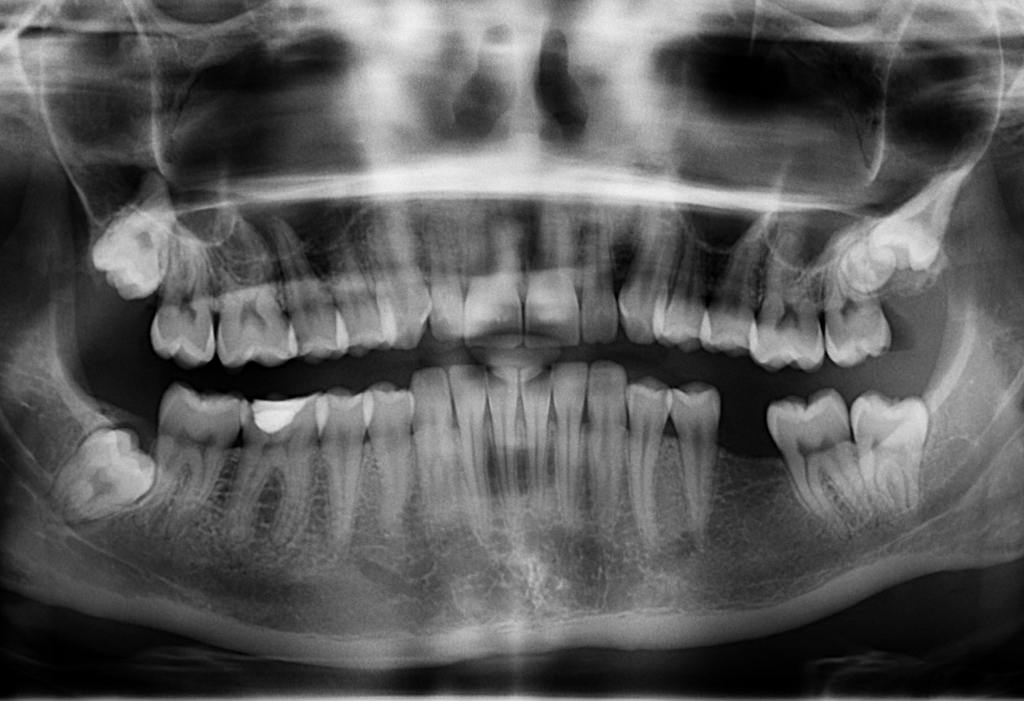

Преступление совершено 17 ноября 2018 года, около 23.40. Рядовой увидел, что его сослуживец ест в неположенное время и несколько раз ударил однополчанина по лицу. Избиение происходило на глазах у других солдат. Потерпевший получил открытый перелом нижней челюсти слева, со смещением отломков. Позже военные следователи расценили это как как вред здоровью средней тяжести.